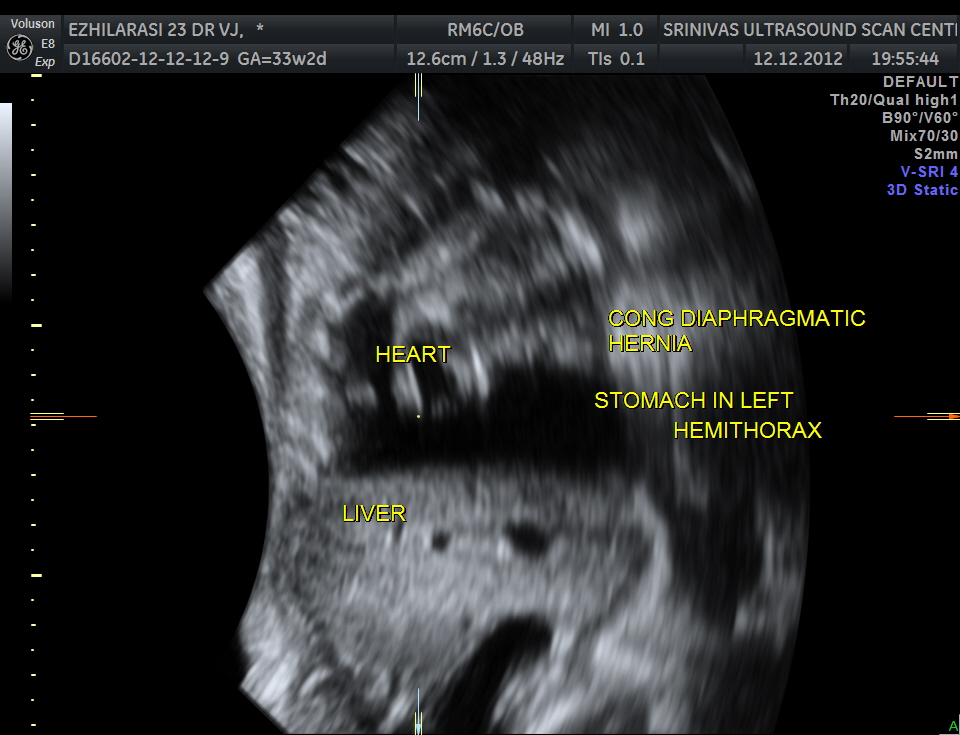

This was a 23 year old primi gravida without history of consanguinity was sent for anomaly scan at 33 weeks of gestation. Earlier two scans had not detected any anomaly at another centre.

The heart was seen in the right side of thorax . The left hemithorax showed the stomach bubble and bowel loops suggestive of Congenital Diaphragmatic Hernia .